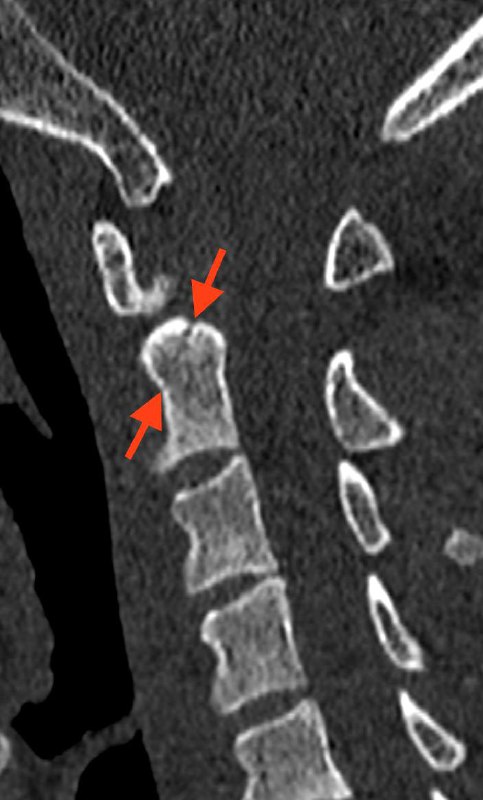

Первый тип перелома зуба C2 и перелом боковой массы атланта справа. Тактика - консервативная.

Кроме того, следует предположить неполное повреждение межостистой связки C4-C5